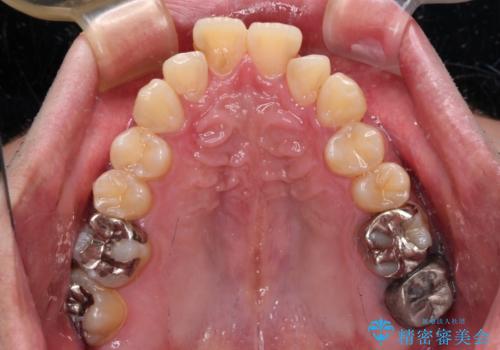

- 主張してる上の前歯を気にして来院された患者様です。

上の前歯が出ているものの、口元が出っ歯というわけではなかったため、非抜歯矯正にて治療を行うこととしました。

下顎に対して上顎歯列が全体的に前方に位置しており、特に右側の奥歯の咬み合わせの前後のズレが大きいため、補助装置を用いて咬み合わせを改善することとしました。